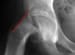

X-ray of a hip following operative percutaneous fixation of a slipped capital femoral epiphysis.